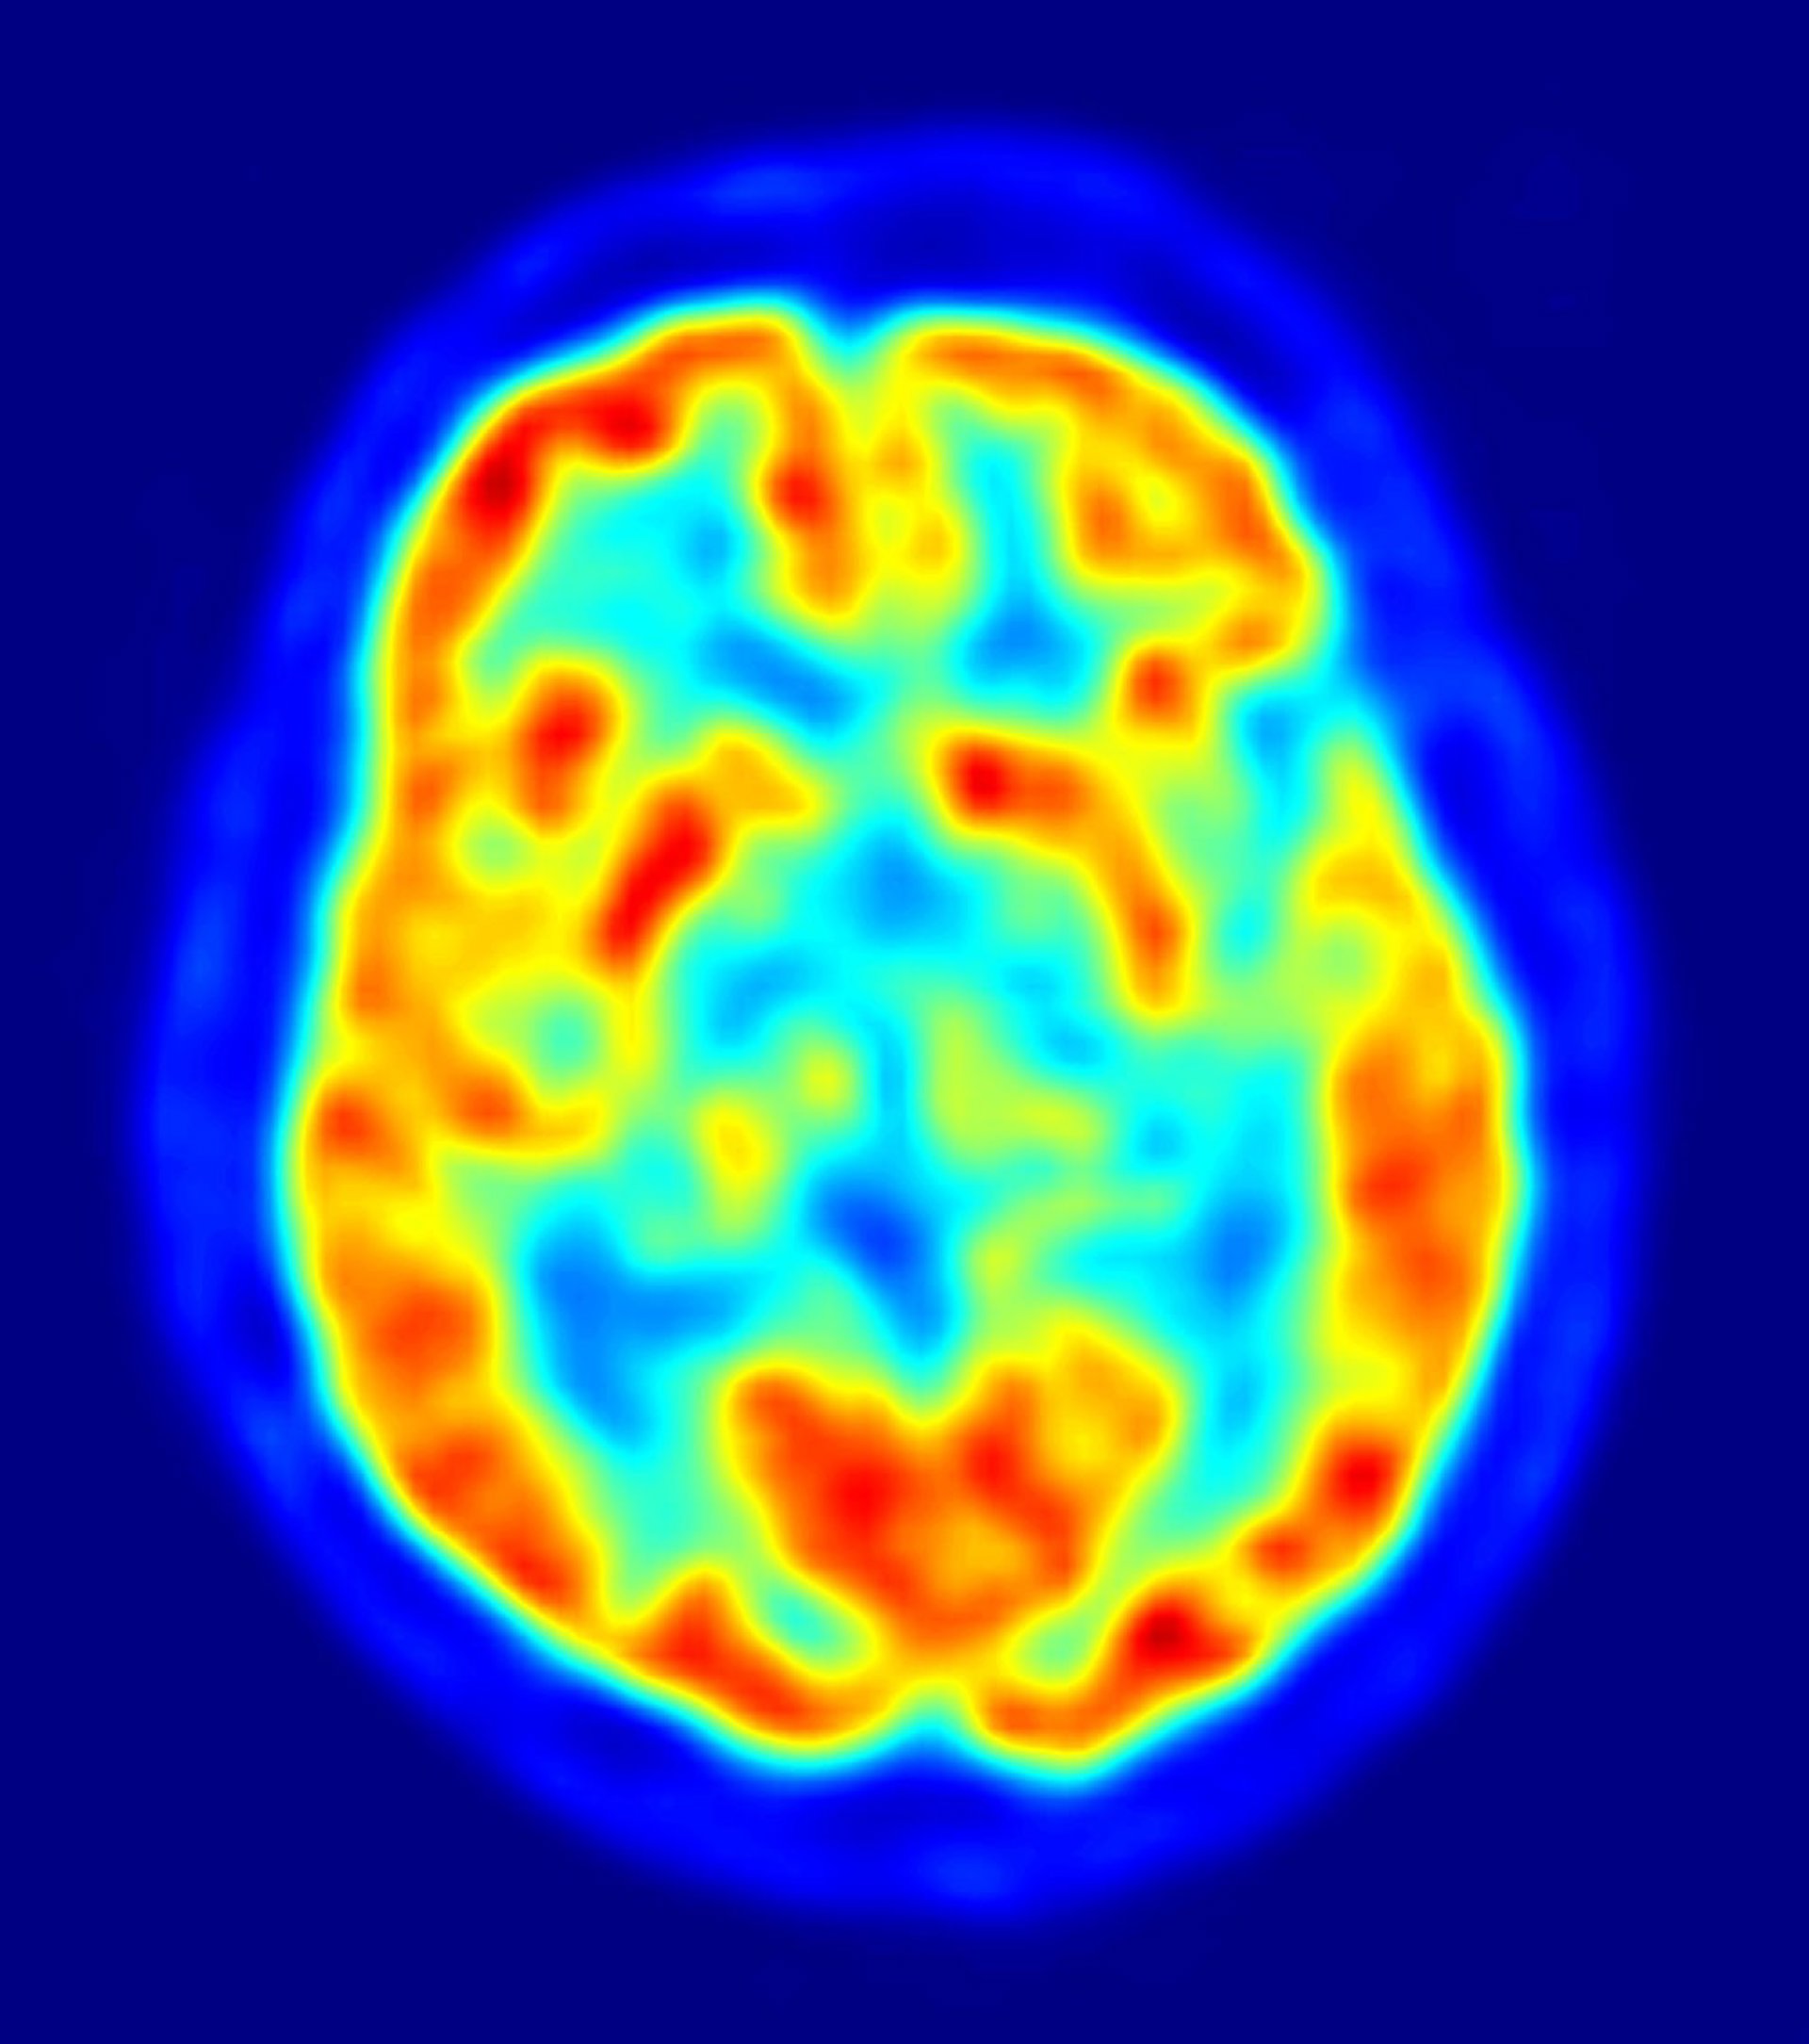

Neurocientíficos de la Universidad de Nueva York han identificado las partes del cerebro que utilizamos para recordar la sucesión de eventos dentro de un episodio. El estudio, que aparece en el último número de la revista 'Science', mejora nuestra comprensión de cómo se procesan los recuerdos y ofrece una guía básica para hacer frente a potenciales trastornos relacionados con la memoria.

Investigaciones anteriores han demostrado que el lóbulo temporal medio del cerebro (MTL) tiene un papel importante en la memoria declarativa, es decir, la memoria de hechos o sucesos, y que los daños en esta área causan un deterioro de la memoria. Más específicamente, la memoria declarativa se encuentra alterada en los pacientes que sufren Alzheimer. Sin embargo, poco se sabe acerca de cómo las estructuras individuales dentro de la MTL recuerdan información sobre cuándo ocurrió un suceso específico, como, por ejemplo, el orden de los brindis en una boda.

Sus resultados mostraron que dos áreas principales del MTL están involucradas en la integración de "qué" y "cuándo": el hipocampo y la corteza perirrinal. El hipocampo, conocido por tener un papel importante en una variedad de tareas de la memoria, proporciona una señal de sincronización incremental entre los eventos clave, proporcionando información sobre el paso del tiempo desde el último evento, así como del tiempo estimado hasta el próximo. La corteza perirrinal integra la información sobre "qué" y "cuándo", qué ocurrió primero o segundo en una serie.